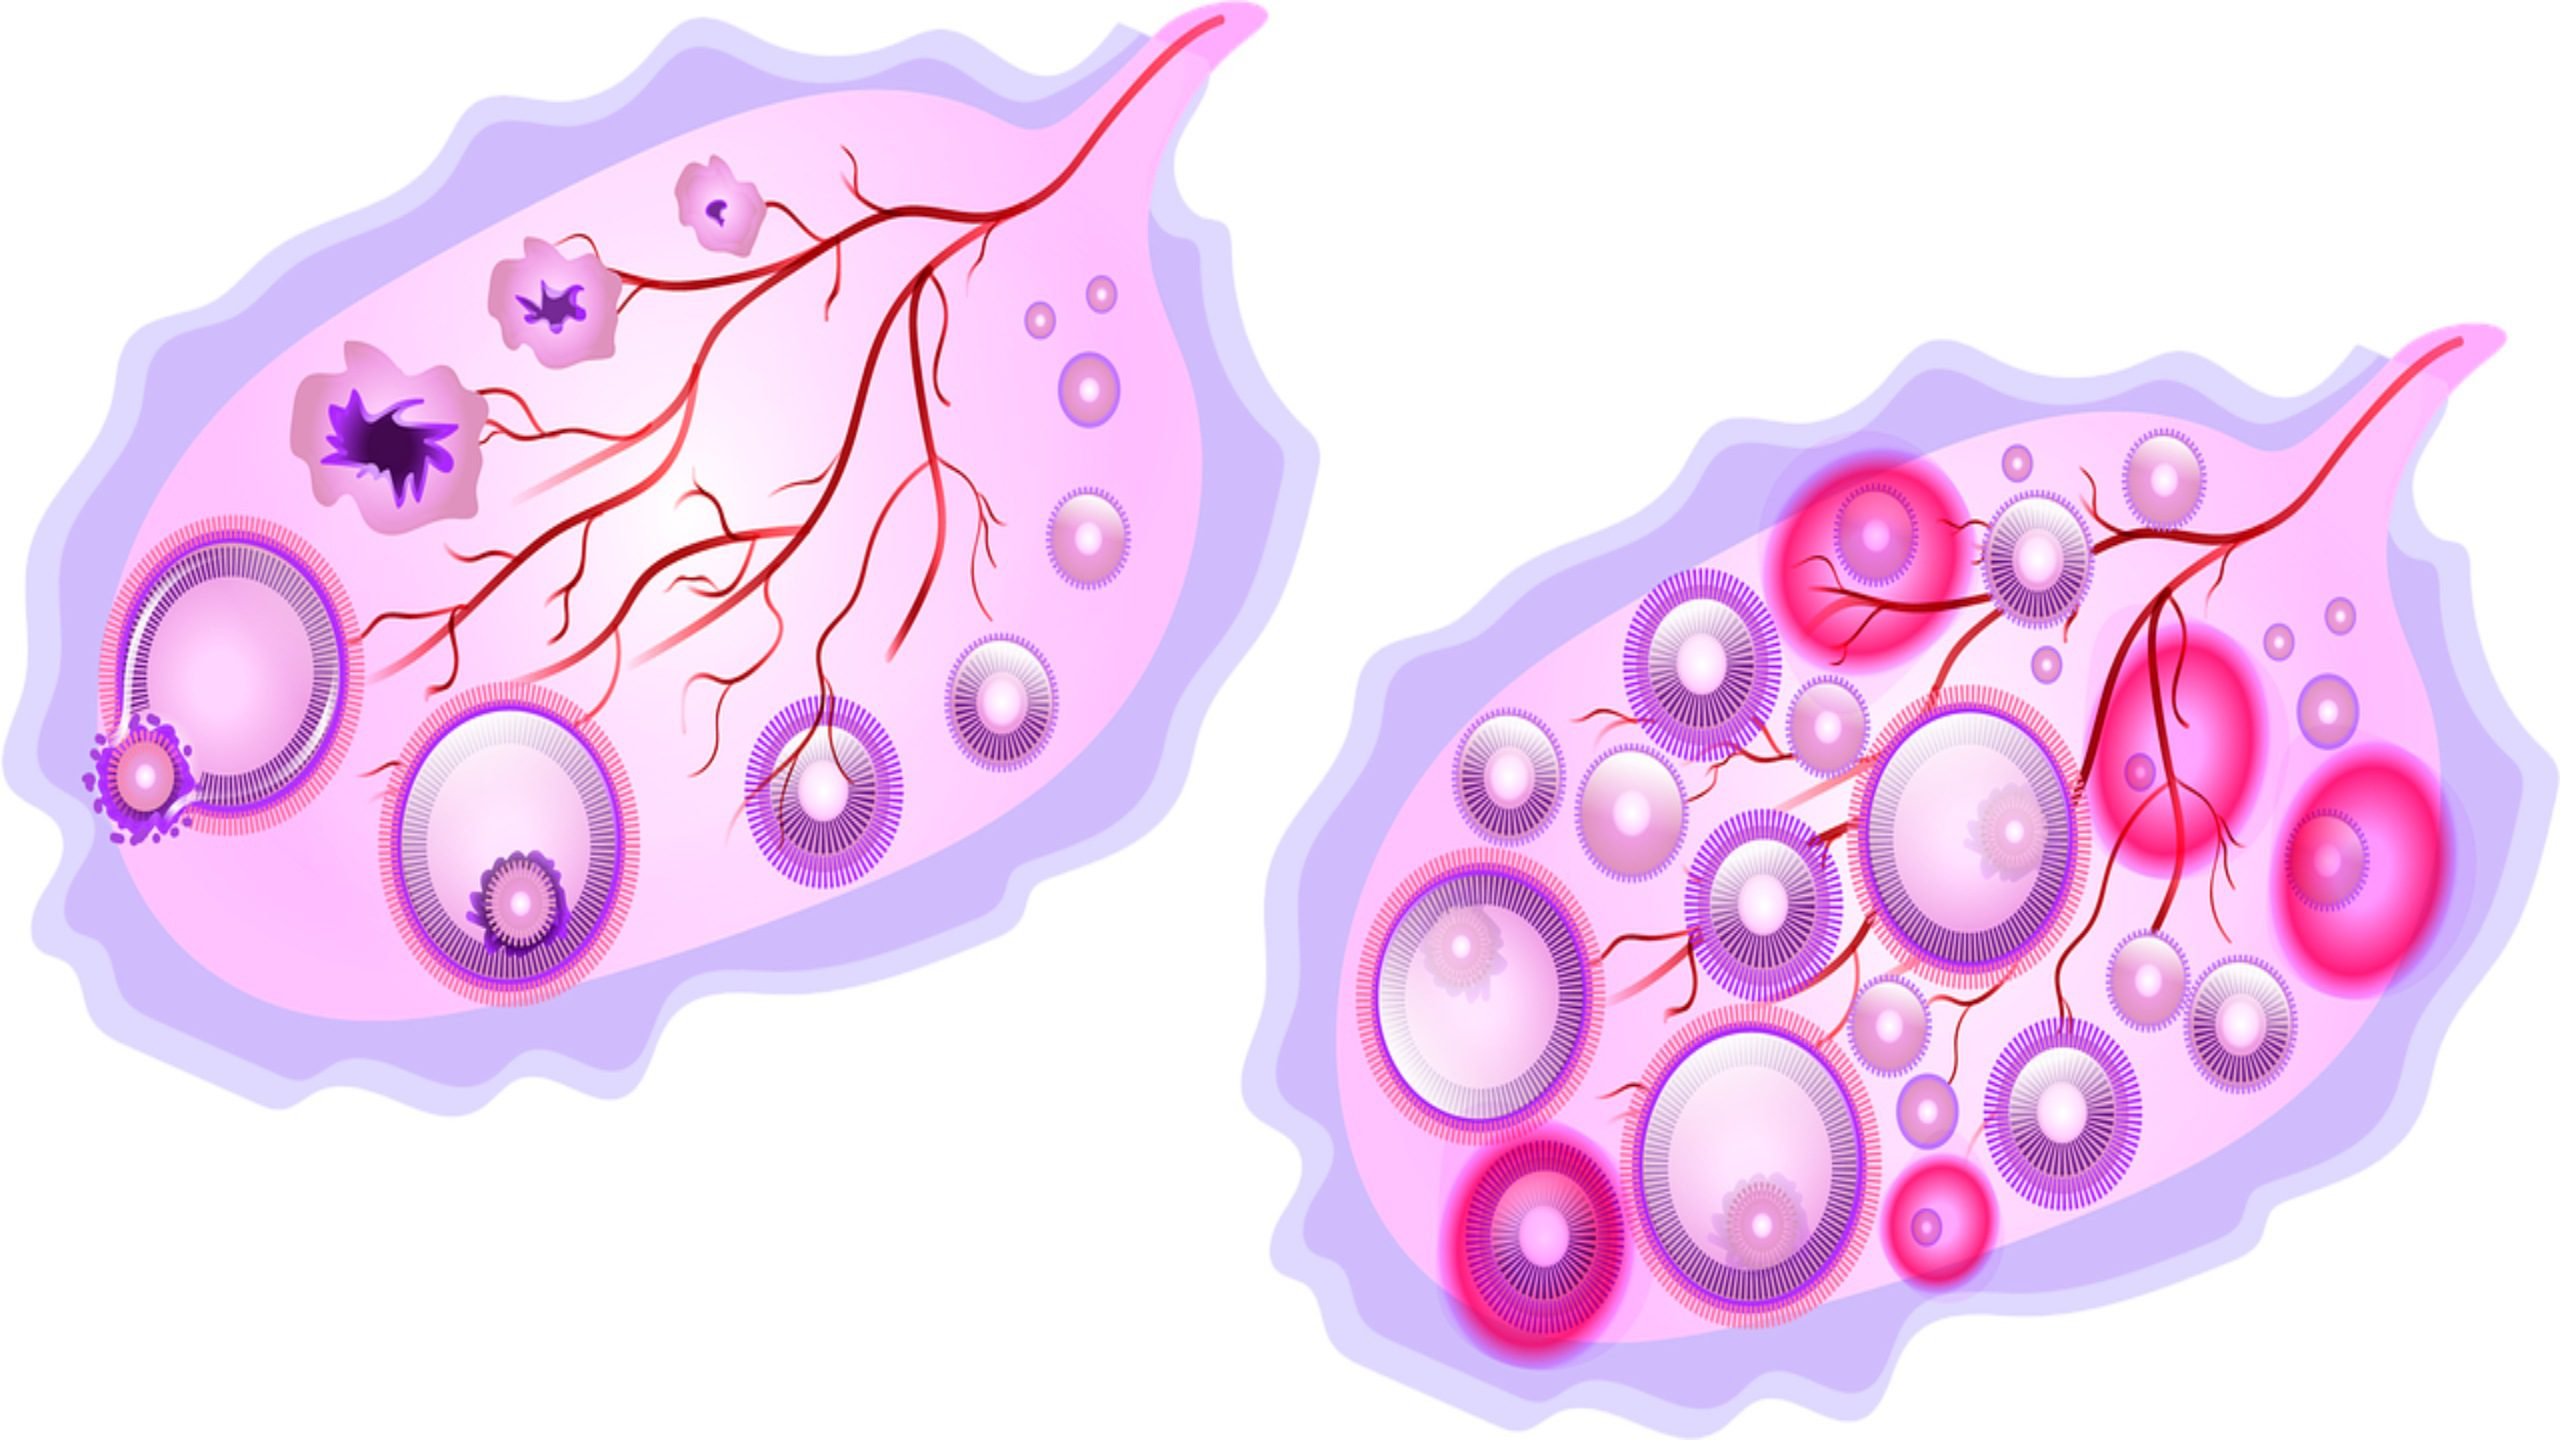

Созревание фолликула в яичнике: этапы и процессы